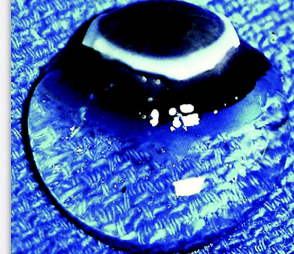

What is the “beaten metal” (peau d’orange) appearance of the lens, and when is it seen?

→ viewed with a slit-lamp using oblique illumination, the anterior capsule of the lens shows a “beaten metal” or “orange peel” (peau d’orange) appearance

occurs because the lens surface is not perfectly smooth, giving it a fine, textured reflection that resembles hammered metal